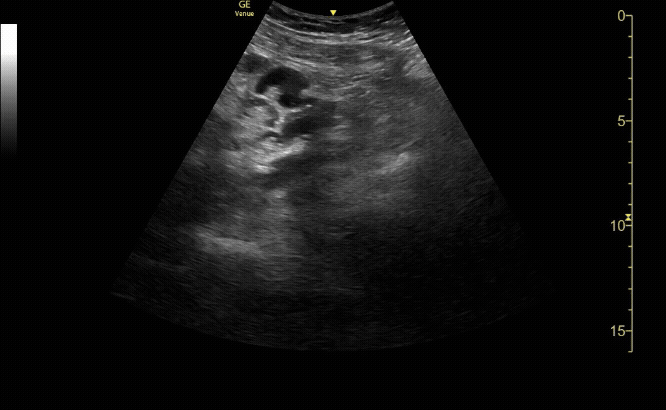

Sagittal view of the uterus with gestational sac, yolk sac, and fetal pole.

c/o Michael Hohl, MD